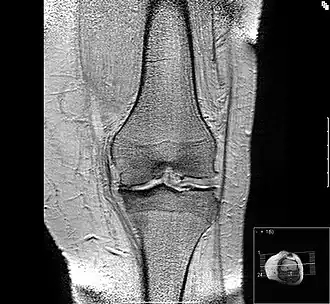

Mediales Kompartiment

In diesem Bild ist erkennbar, dass der Knorpel im innenseitigen (medialen) Bereich des Gelenkes aufgebraucht ist und im medialen Bereich des Schienbeinkopfes der unter dem Knorpel gelegene Knochen verdichtet ist. Dies wird „sklerosiert“ oder „eburnisiert“ genannt. Sowohl im seitlichen (lateralen) als auch im medialen Gelenkanteil ist es zu osteophytären Reaktionen gekommen. Der Körper versucht, durch eine Verbreiterung der Auflagefläche den auf den Gelenkknorpel lastenden Druck zu mindern. In der höheren Auflösung sind auf diesem Bild die Muskelzüge um das Knie deutlich zu sehen, in der verkleinerten Abbildung kommt das nicht zur Darstellung. Durch die „Höhenminderung des medialen Gelenkspaltes“ (klinischer Jargon, gemeint ist die Höhenminderung des Knorpels) kommt es zu einer Fehlstellung des Kniegelenkes, das Bein weicht in die Varus- oder O-Fehlstellung ab. Die Lotlinie vom Hüftkopf durch das Sprunggelenk wandert aus dem Zentrum des Knies in Richtung mediales Kompartiment aus, der Auflagedruck in dem schon verschlissenen Teil des Gelenkes nimmt weiter zu, das Krankheitsbild verschlimmert sich selbst.